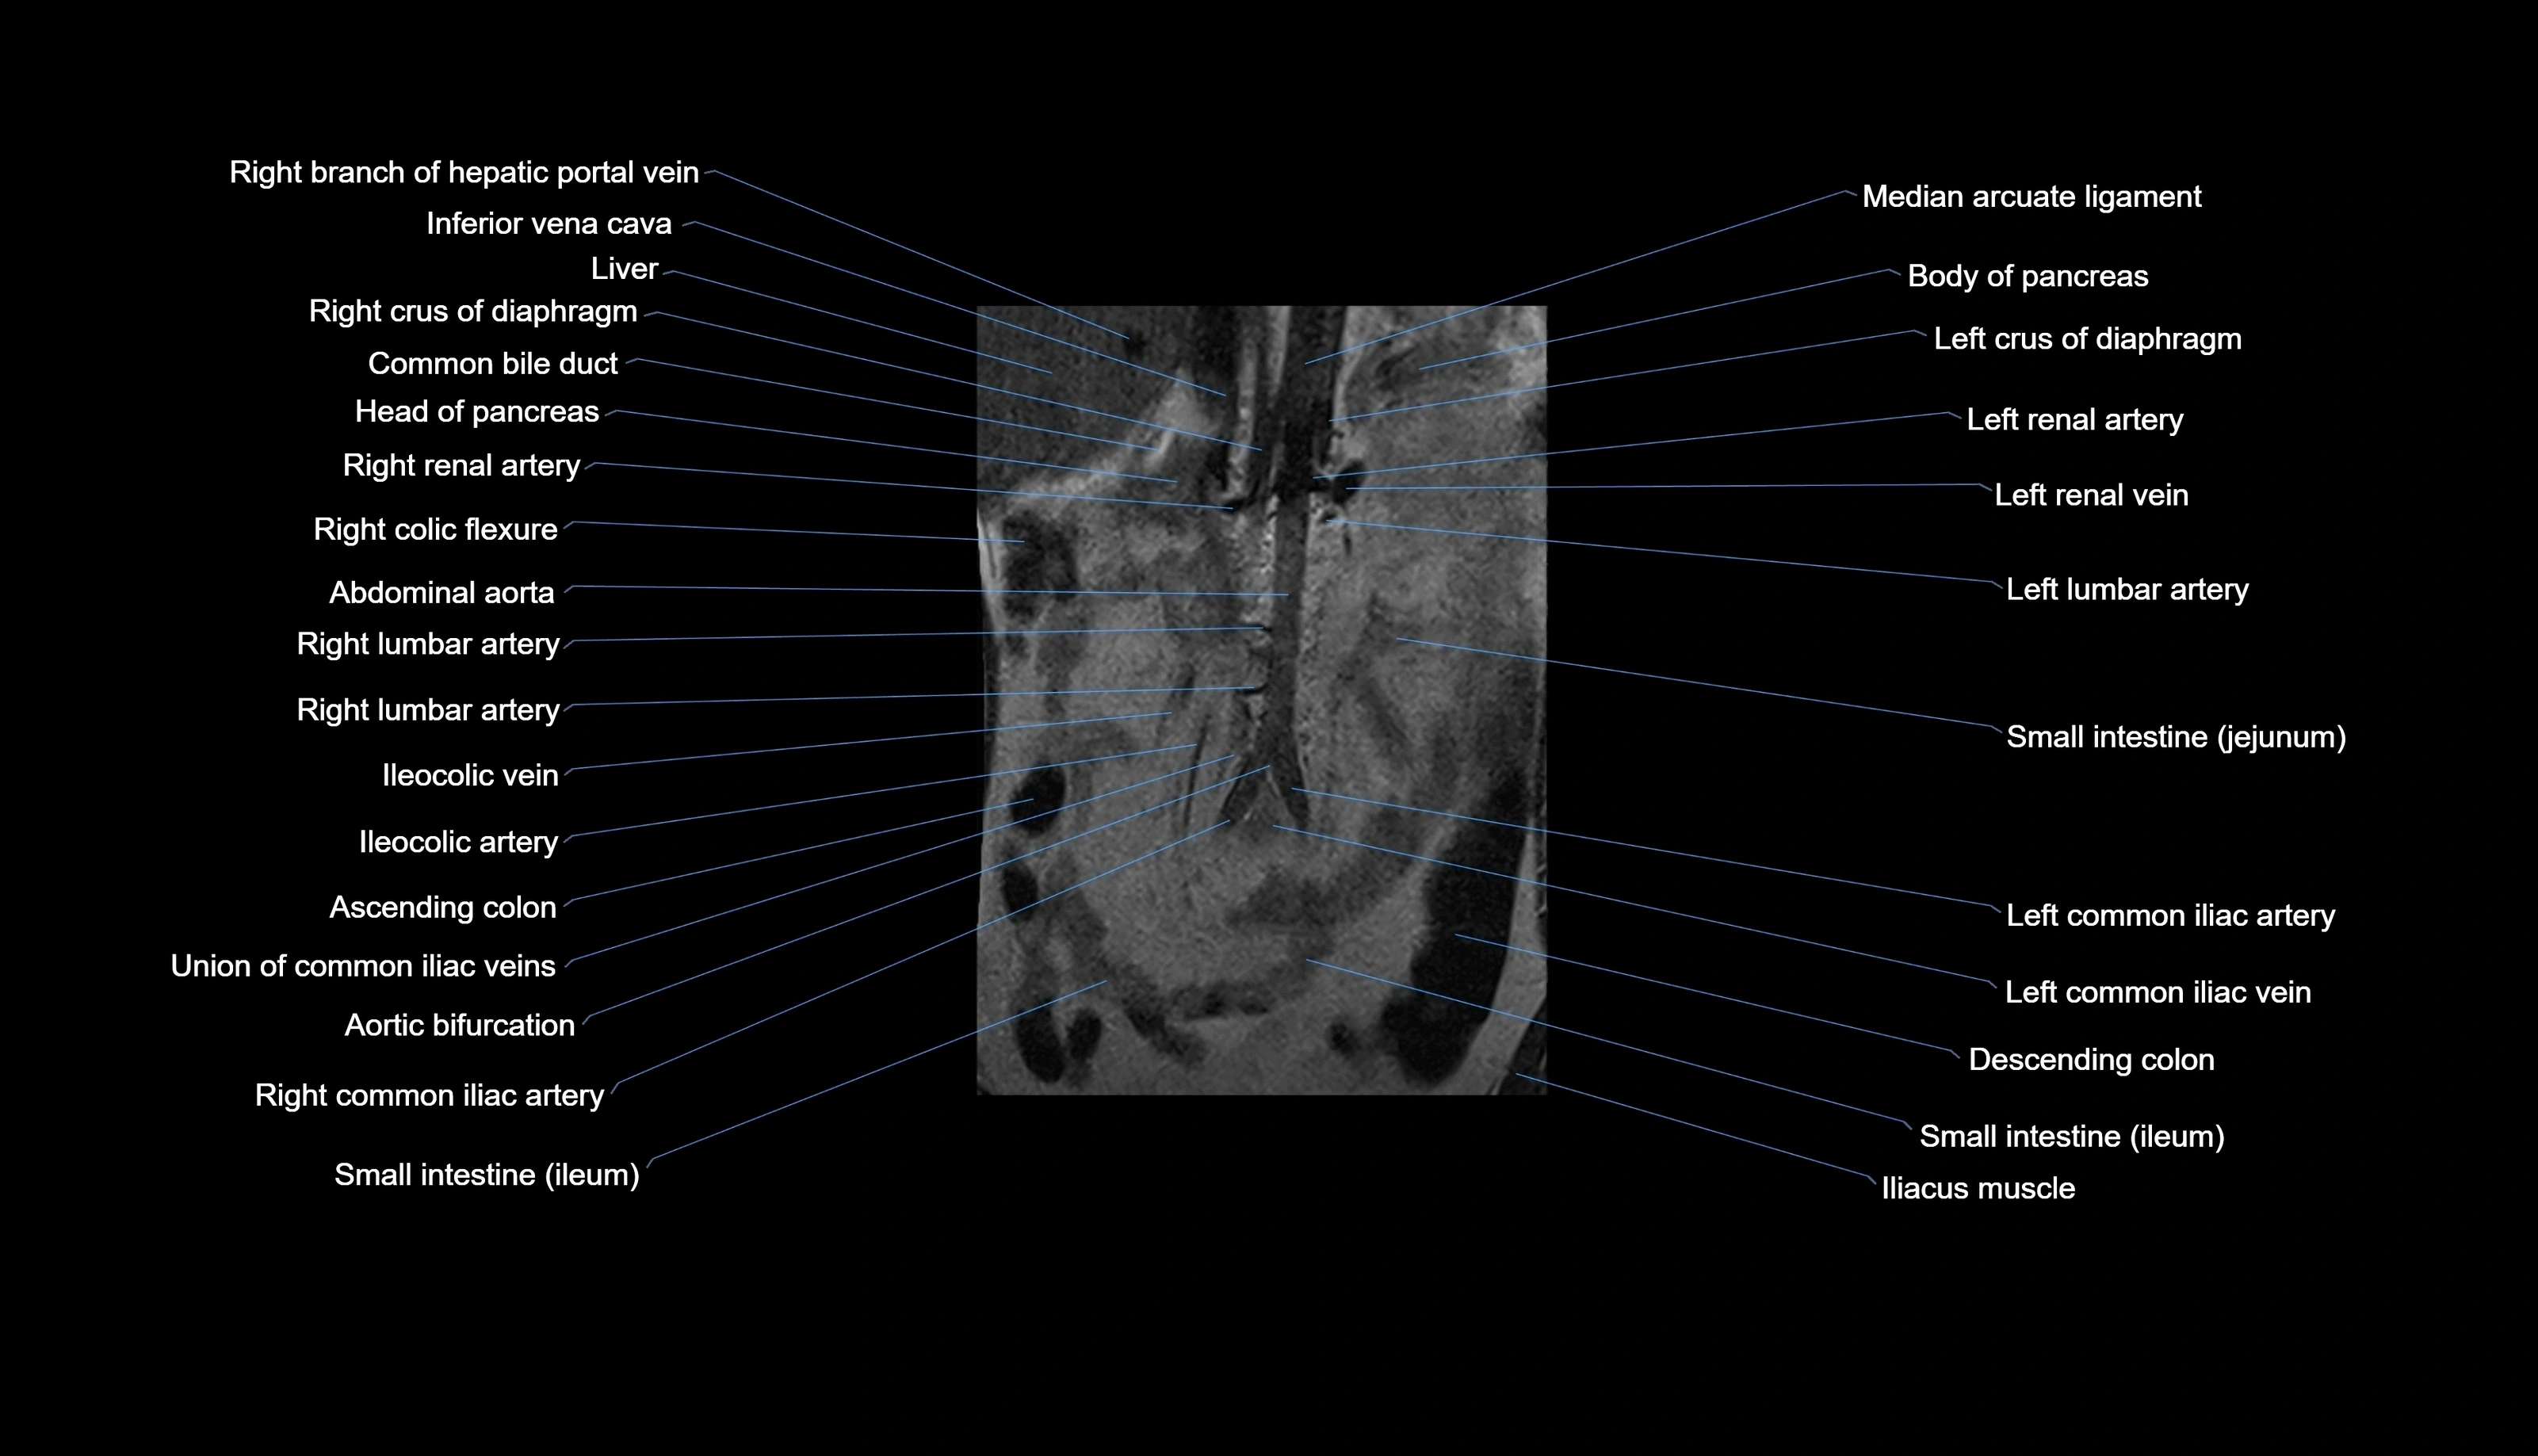

MRI images